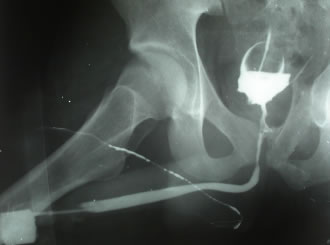

- Восходящая уретрография - остановка

контраста в перепончатом отделе уретры. Контраст

не поступает в мочевой пузырь

- Микционная цистография - дилятация

простатической уретры, деформация и сужение перепончатой

уретры. Мочеиспускание очень слабой струей.

Контрольная восходящая уретрограмма – уретра

проходима на всем протяжении. |